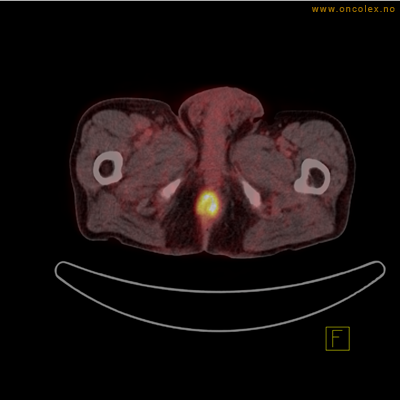

Høyt opptak av 18F-FDG ved analkreft.

Høyt opptak av 18F-FDG i adenokarsinom i rektosigmoideumovergangen. Fysiologisk opptak i blæren.